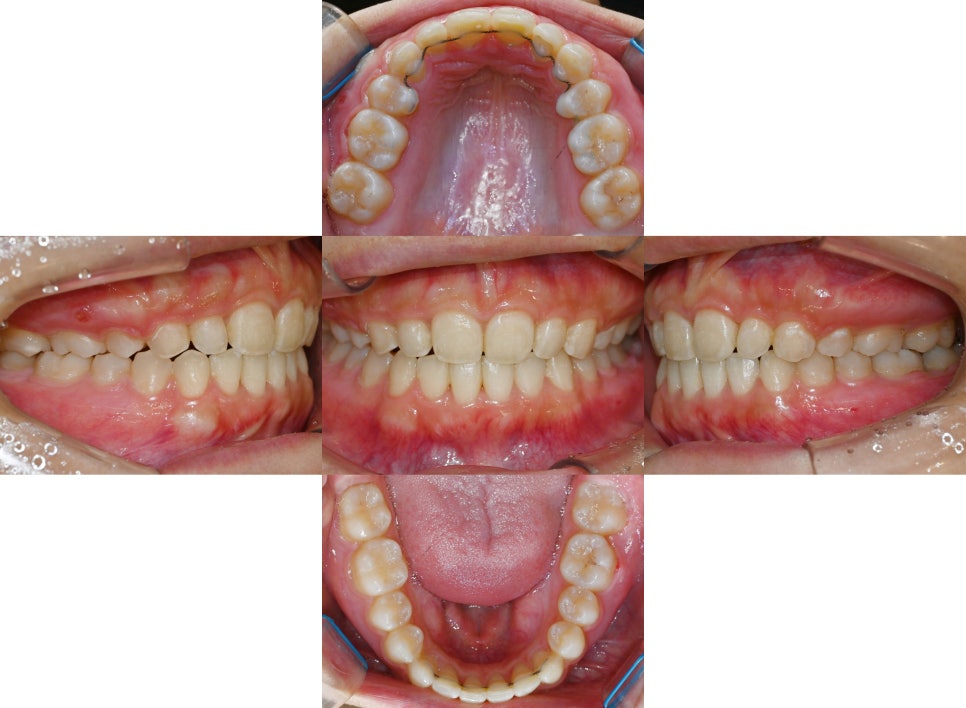

모든 치료 과정이 끝나고 나면

아랫니가 거의 덮여 보이지 않던

초진 때와 달리 예쁜 아래 앞니가 잘 보입니다.

이에 맞춰 어금니 맞물림 역시

어긋남과 불편함 불편함 없이

올바르게 작용할 수 있도록 잘 맞춰져 있습니다.

또한, 돌출되어 나와 보였던 21번도

이제는 후방으로 잘 견인되어

틀어짐 없이 잘 정렬되어 있습니다.

구외 사진을 보면 정중선이 맞고

깔끔히 정리된 모습을 볼 수 있습니다.